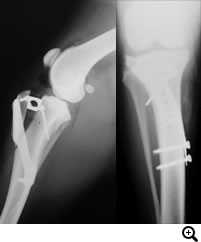

THR(Total Hip Replacement)/ 股関節全置換術

Micro THR(Micro Total Hip Replacement)/ 小型犬・猫用股関節全置換術

全股関節置換術は股関節形成不全やその他の股関節の異常(レッグペルテス、骨頭骨折等)に対して行われる根治的治療法で、機能の回復に関しては現在のところ最もすぐれた治療法です。機能しない、あるいは痛みを持つ股関節をチタンの人工関節に取り替える方法です。6カ月齢からあらゆる年齢で可能な手術です。